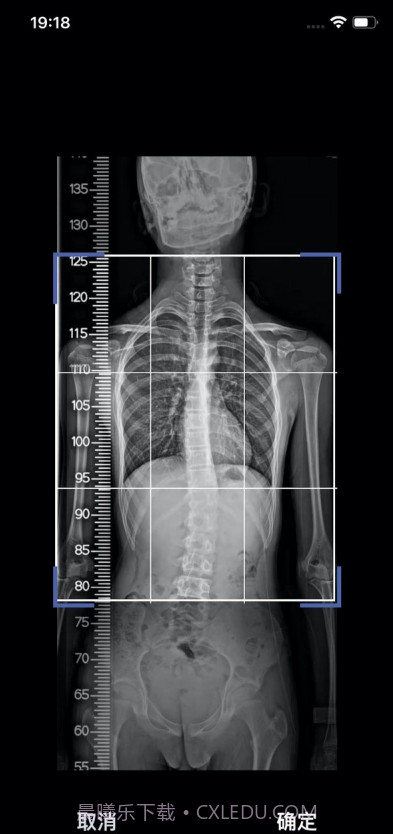

筠成矫形真的是一款很贴心的健康管理应用,特别适合坐办公室的白领和有姿势问题的青少年。它的个性化脊椎矫正方案通过摄像分析脊柱状况,真的能让你一目了然地看到自己的姿势问题。这款应用解决了不少人面对健康管理时的困扰:不再需要频繁去医院检查,你只需在家用手机拍照,就能获得专业的建议和提醒。最重要的是,它的定时休息提醒功能可以有效帮你避免久坐造成的健康隐患。总之,使用这款应用,你会发现自己更关注健康,生活质量也会随之提升!

摄像分析功能科技感十足,画面清晰

使用摄像头拍摄分析,科技感满满